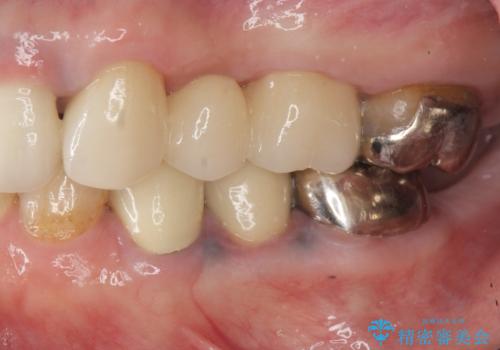

- 39.6万円(ジルコニアクラウン×3・仮歯×3)費用は治療当時の料金となります

ジルコニア製セラミックブリッジは、審美性にすぐれた補綴方法です。